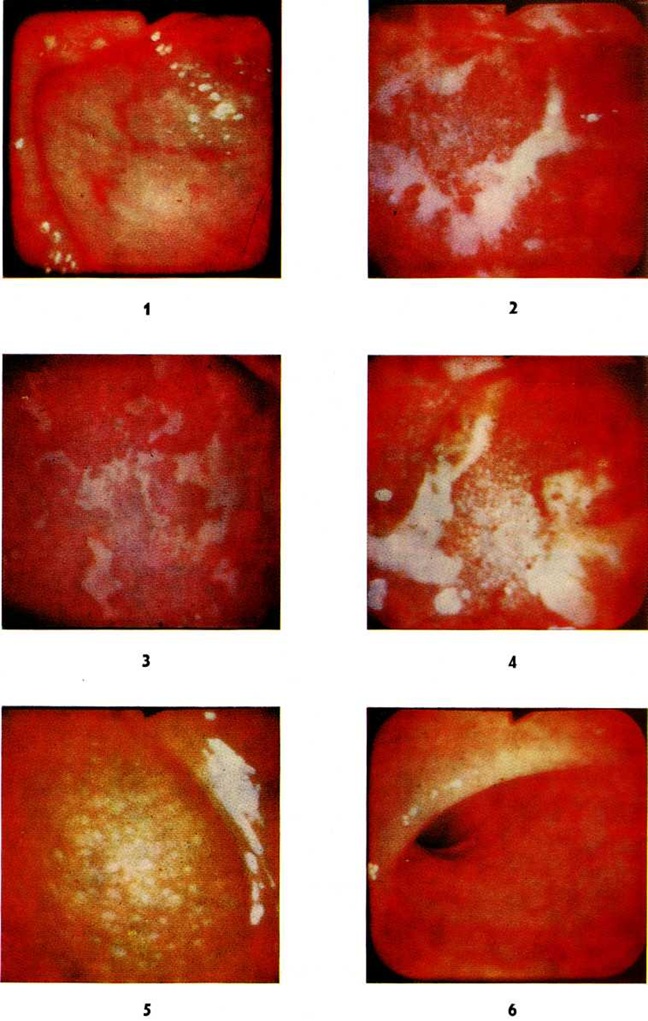

ПроктитПроктит (proctitis; греческий proktos задний проход, прямая кишка + -itis) — воспалительный процесс, поражающий преимущественно слизистую оболочку прямой кишки. Проктит протекает остро, подостро и хронически (смотри полный свод знаний: Воспаление). При остром течении выделяют катаральную, гнойную, язвенную, язвенно-некротическую формы (цветной рисунок 1—4), а также фибринозную и геморрагическую. Возбудитель инфекции может проникать в прямую кишку различными путями: через рот (дизентерия, холера и другие), гематогенно, через задний проход (гонорея, мягкий шанкр, паховый лимфогранулематоз), при огнестрельных или других ранениях, с инородными телами. При таких заболеваниях прямой кишки и соседних органов, как геморрой, парапроктит, полипы и рак прямой кишки, абсцесс дугласова пространства, простатит, цистит, вагинит может наблюдаться вторичный проктит. Проктит может являться проявлением инфекционные поражения всей толстой кишки (при дизентерии, холере и другие); отравления ядами, грибами; микотического поражения при длительном лечении антибиотиками либо проявлением воспаления ограниченных отделов кишки, например, при хронический колитах, сопровождающихся запорами (застойный проктит). Возможен также проктосигмоидит, сфинктерный Проктит (анит), например, при трещине заднего прохода, папиллит, наблюдающийся при воспалении анальных сосочков (рисунок), криптит, при воспалении морганиевых крипт (смотри полный свод знаний: Задний проход). Длительно текущий, трудно поддающийся лечению лучевой Проктит нередко наблюдается после лучевой терапии злокачественных опухолей органов таза (смотри полный свод знаний: Лучевые повреждения). Острый Проктит проявляется постоянными болями в прямой кишке, непроизвольным истечением из неё серозных, гнойных, слизистых, геморрагических выделений, повышением температуры тела. Функция кишки нарушена: наружный сфинктер заднего прохода ослаблен, нередко задний проход зияет. Постепенно под влиянием лечения симптомы острого Проктит стихают, может наступить выздоровление или Проктит переходит в подострую либо хронический стадию. Примесь слизи в каловых массах или обнаружение её при ректороманоскопии свидетельствует о незаконченном воспалительном процессе. В исходе острого проктита, особенно гонорейного, а также язвенного, возможны рубцовые сужения прямой кишки. Диагноз Проктит базируется на данных осмотра области заднего прохода, ректального исследования (смотри полный свод знаний), ректороманоскопии (смотри полный свод знаний). При исследовании обнаруживается гиперемия, отёчность слизистой оболочки кишки. Характерны наложения слизи, фибрина, кровоизлияния, кровоточивость, изъязвления. Важную роль в диагностике воспалительных заболеваний прямой и сигмовидной кишок имеет цитологический исследование кишечного содержимого. Лечение острого и подострого Проктит следует начинать с устранения вызвавших его причин. Рекомендуют постельный режим, ограничение употребления пищевых продуктов, содержащих много клетчатки, исключают жареные, острые блюда, запрещают приём спиртных напитков. Пища должна быть механически щадящей. Назначают антибиотики, сульфаниламиды, тёплые клизмы 2—3 раза в день с раствором перманганата калия, риванола, 2% раствором колларгола или протаргола, с настоем ромашки или с рыбьим жиром. Хорошие результаты даёт введение в прямую кишку пенообразных антисептиков. Полезны сидячие ванны и промежностные тёплые души с антисептическими растворами. Прогноз чаще благоприятный. Однако в ряде случаев при несвоевременно начатом лечении возможен переход в хронический форму. Хронический Проктит имеет три основные формы — гипертрофическую, нормотрофическую и атрофическую. При гипертрофической форме эндоскопически отмечаются утолщённые, отёчные, иногда избыточно разросшиеся рыхлые складки слизистой оболочки с несколько увеличенными легко различимыми лимфатических, фолликулами (цветной рисунок 5). При нормотрофической форме складки слизистой оболочки имеют нормальный вид. При атрофической форме (цветной рисунок 6) слизистая оболочка прямой кишки истончена, сухая со сглаженными складками и просвечивающими сосудами, легко ранима. При всех формах хронического Проктит нередко субъективные ощущения отсутствуют, в каловых массах обнаруживается небольшая примесь слизи. При бессимптомном хронический Проктит больные редко обращаются к врачу. |